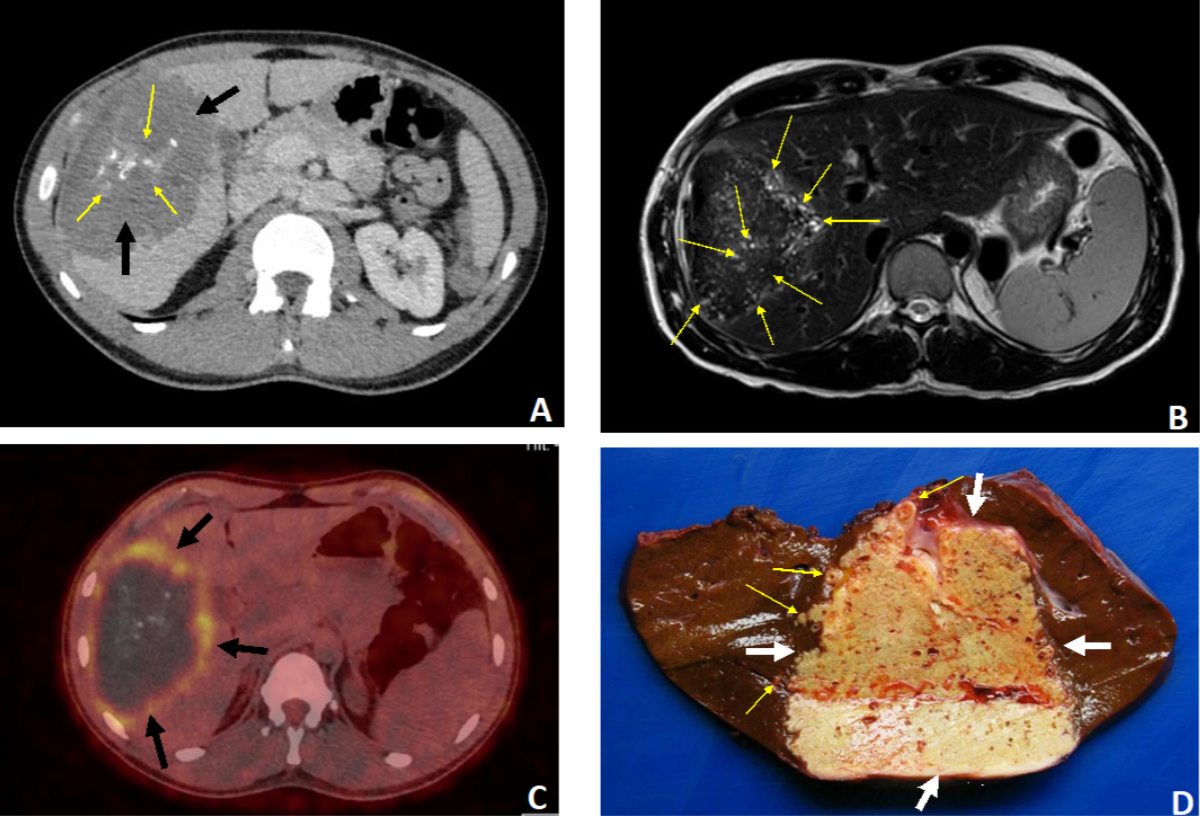

Figure 337-year-old patient. Discovery of hepatic alveolar echinococcosis (AE) classified as P2N1M0 (stage IIIb) due to right hypochondrial pain. A–C: Radiological aspects of the lesion invading the right lobe (segments IV, V, VI and VII). A: Non-contrast CT scan, axial section: huge AE lesion (11 cm in greatest axis) with heterogeneous content, central “crumb-like” calcifications (thin arrows) and a hypodense peripheral component (thick arrows). Ill-defined margins. B: MRI, T2-weighted sequence, axial section. Presence of numerous hyper-T2 microcysts within the lesion (arrows), indicative of the florid nature of AE. C: PET-CT axial section: intense perilesional uptake of 18 fluorodeoxyglucose (arrows), an indirect sign of an active AE. D: Right hepatectomy specimen, macroscopic view: the AE lesion is located at the centre of the surgical specimen (thick arrows). Chamois yellow in colour, it is filled with numerous small cavities corresponding to parasitic microcysts. The lesion has irregular limits and extends into the healthy hepatic parenchyma (thin arrows).